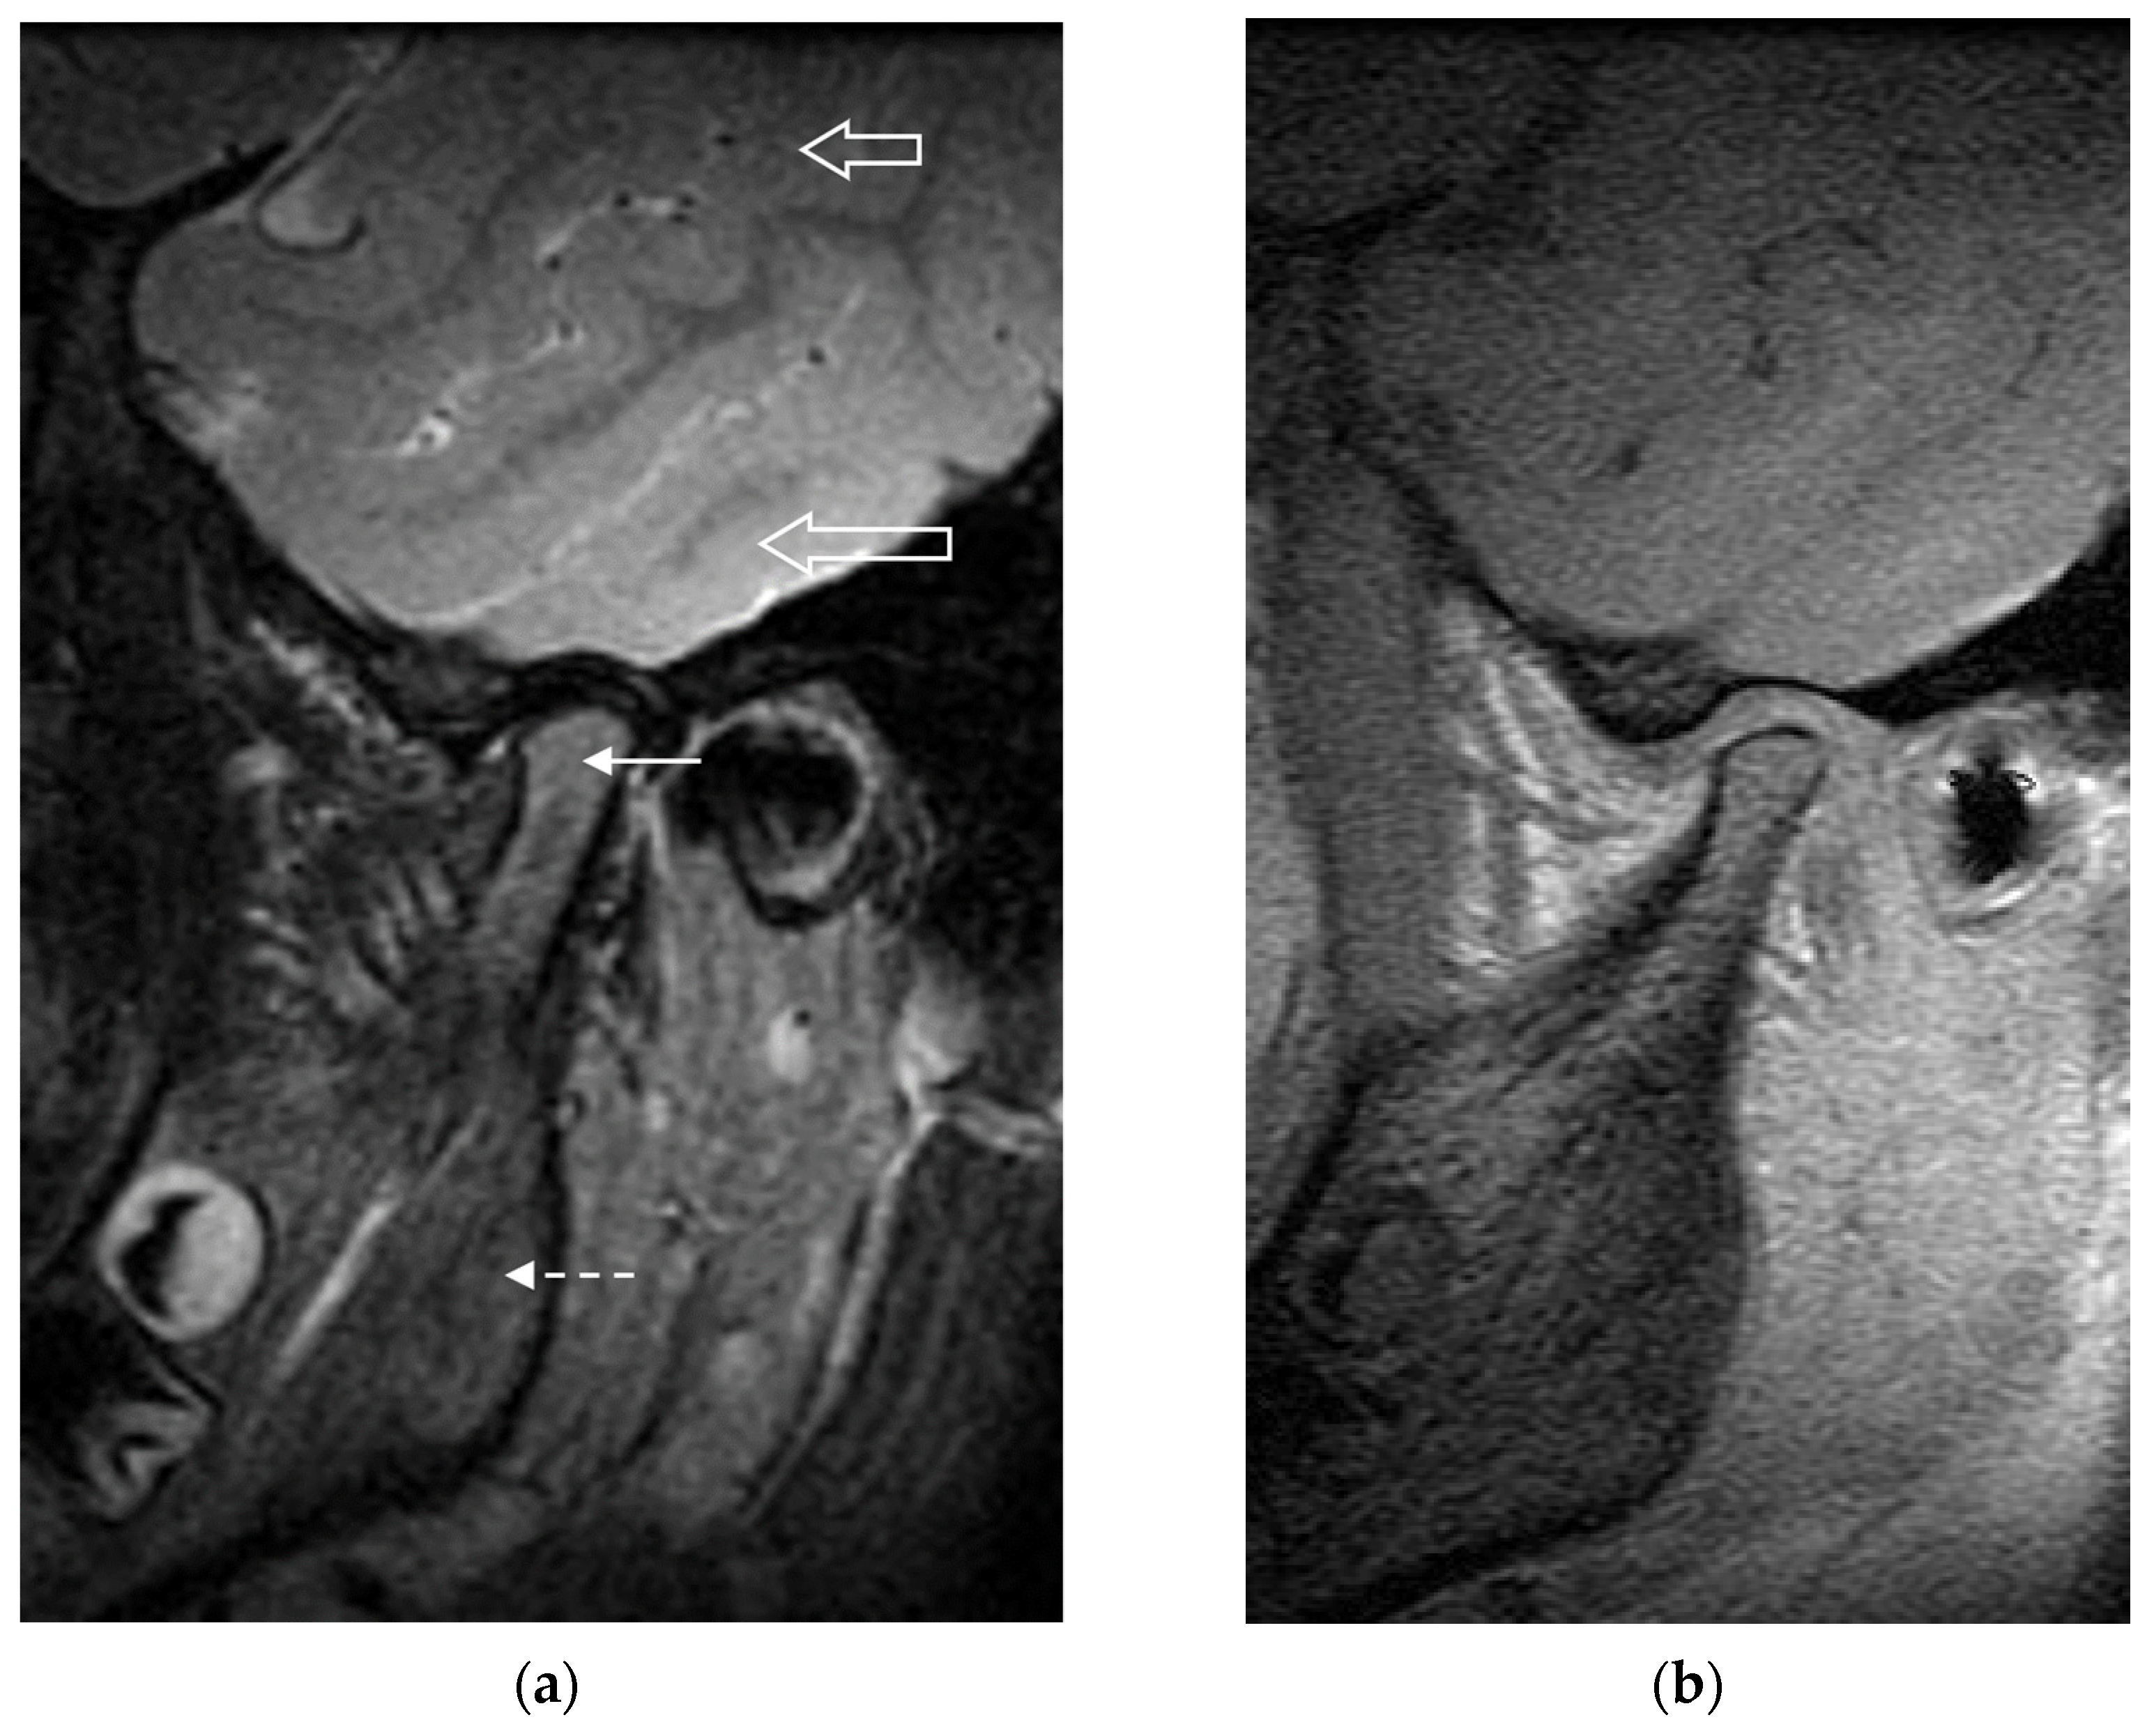

| INFLAMMATORY DOMAIN | |||||

| Definition | Bone Marrow Edema | Bone Marrow Enhancement | Effusion | Synovial Thickening | Joint Enhancement |

| Compared to the mandibular ramus, hyperintense marrow signaling within the condyle on T2w FS or STIR images, and/or hypointense signaling on pre-contrast T1w images without FS. | Compared to the mandibular ramus, hyperintense marrow signaling within the condyle on post-contrast T1w FS images. | Increased joint fluid with isointense signaling of joint space compared to that of cerebrospinal fluid on T2w FS or STIR images. | Thickened synovial lining of the TMJ with intermediate signal on T2w images. | Signal intensity of the synovium, capsule, and joint fluid higher than that of muscle on post-contrast T1w FS images. | |

| Grading | Absent | Absent | Normal: ≤1mm fluid in joint recess | Absent: No synovium visible (joint space ≤1 mm width) | Normal: High signal intensity confined to signal perimeter of normal amount of joint fluid on corresponding fluid-sensitive image |

| Present | Present | Small: >1 and ≤2mm fluid in recess or involving entire joint compartment | Mild: >1 and ≤2mm thickness at the point of maximum synovial thickening | Mild: High signal intensity focally exceeding signal perimeter of physiologic amount of joint fluid on corresponding fluid-sensitive image | |

| Large: >2mm fluid in recess or involving entire joint compartment | Moderate/Severe: >2mm thickness at the point of maximum synovial thickening | Moderate/Severe: High signal intensity diffusely involving one or both joint compartments | |||

| DAMAGE DOMAIN | |||||

| Definition | Condylar Flattening | Erosions | Disk Abnormalities | ||

| Loss of the round or slightly rectangular shape of the condylar head, viewed in the sagittal-oblique plane. | Any irregularity or breaks of the bony joint surfaces leading to the loss of the smooth continuous surface of the bone, seen in both sagittal and coronal planes | Any abnormality of the articular disk, including flattening, displacement, or destruction. | |||

| Grading | Normal round/slightly rectangular shape | No irregularities or deep breaks | Absent | ||

| Mild: Extent of flattening involves part of the surface of the condyle | Mild: Presence of irregularities involving only part of the articular surface of the condyle | Present | |||

| Moderate/Severe: Extent of flattening involves the entire surface of the condyle, or loss of height in the condyle. | Moderate/Severe: Presence of deep breaks in the subchondral bone seen in two planes, or irregularities involving the entire articular surface of the condyle | ||||